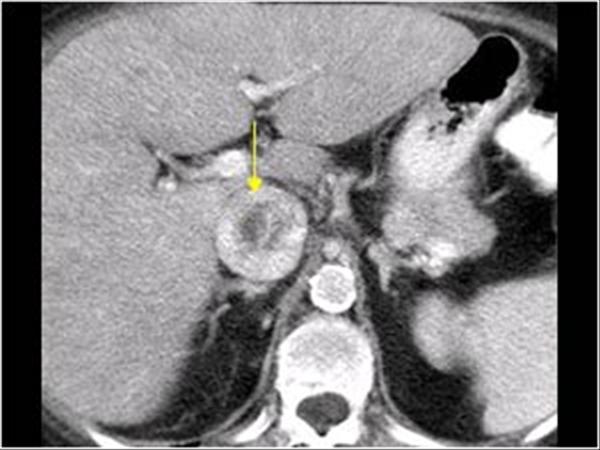

RCC

» Thông tin: Nữ giới – 69 tuổi.

» Lâm sàng: Đái máu.

# Ung thư biểu mô tế bào thận phải (Renal cell carcinoma – RCC) / Huyết khối tĩnh mạch chủ dưới.